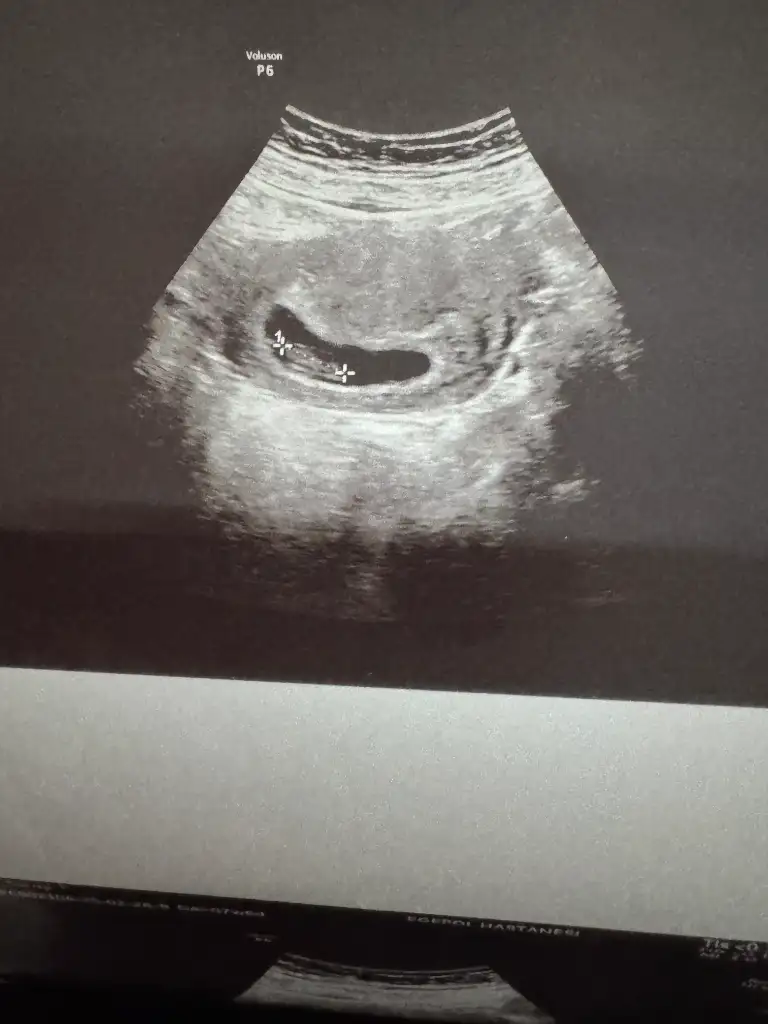

10. Haftada baya büyümüş oluyor ya ben bugün şok oldum görünce. Az kaldı dayannnYaaazaman çok çabuk geçsin istiyo insan bu durumlarda. Sağlıkla büyüsün bebişlerimiz